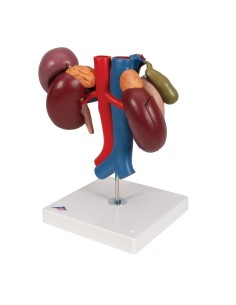

Dal cranio in 22 parti con incastri magnetici ai modelli di colonna vertebrale, da quelli di articolazioni a quelli di cuore, ogni pezzo della nostra collezione è progettato per un’immersione totale nello studio dell’anatomia umana. I nostri modelli, realizzati tramite scansioni di ossa vere, garantiscono un’esperienza tattile autentica e una fedeltà di peso quasi identica agli originali.

Essenziali per studenti e professionisti, i nostri modelli anatomici sono strumenti didattici che permettono di osservare le strutture anatomiche con precisione, eliminando la necessità di dissezioni o studi invasivi. Sono inoltre utili per spiegare ai pazienti le patologie, rendendo la comunicazione più efficace e risparmiando tempo prezioso.